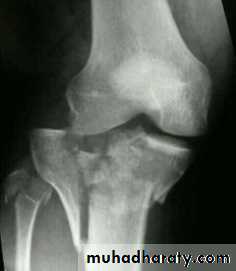

Tibial plateau fractures:

Direct blow or fall from height may cause fracture of one tibial condyle or both.

Fracture lateral condyle is the commonest named as bumper fracture

caused by a force that abducts the tibia upon femur while the foot is fixed on ground.

Patient usually is an adult, the knee joint is swollen, bruises, there is diffuse tenderness and doughy feel of haemarthrosis.

ligaments injuries must be excluded.

Imaging : X-ray

: anteroposterior, lateral & oblique views.

CT -Scan may used to detect amount of depression and comminuation.

Tibial plateau fracture